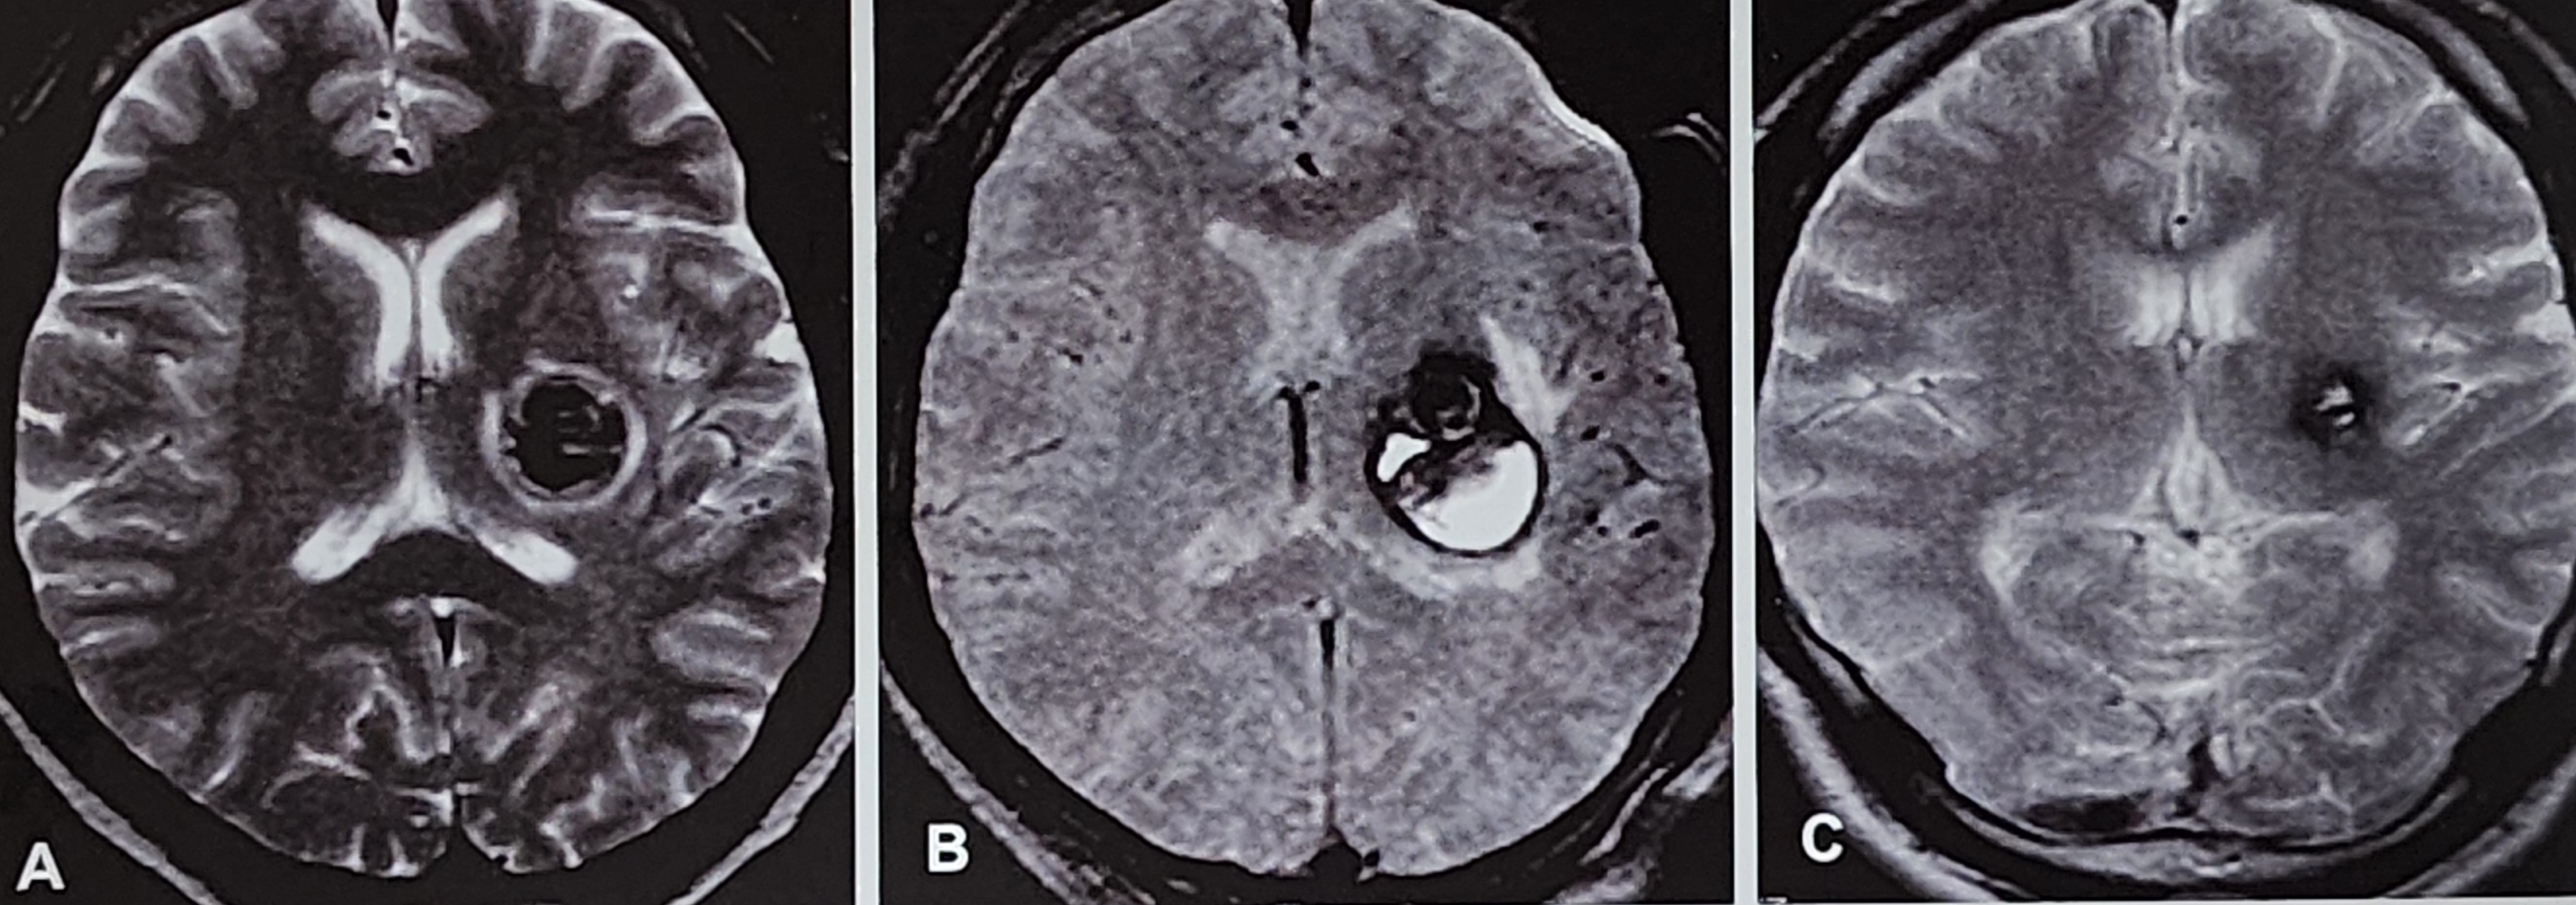

해면상 혈관종은 뇌에 존재하는 비정상적인 혈관 덩어리로, 일반적으로 모세혈관 크기의 혈관들이 뭉쳐 형성된 병변이다.

전체 뇌혈관기형 중 약 5~13%를 차지하며, MRI 영상에서 특유의 '팝콘 모양'으로 보이기도 한다.

이 병변은 증상이 없을 수도 있지만, 출혈이나 간질, 신경학적 결손 등을 유발할 수 있으며, 특히 뇌간, 시상, 심부 구조에 위치할 경우 수술적 제거가 어려워 보존적 관리가 일반적이다.

방사선수술은 비침습적 치료법으로, 병변에 고용량의 방사선을 정확히 조사하여 서서히 혈관을 폐쇄시키는 원리로 작용한다. 수술이 불가능한 부위에 위치하거나, 반복적인 출혈이 있는 환자에게 적용되며, 병변 크기가 작을수록 치료 효과가 좋다. MRI를 기반으로 치료 계획이 수립되며, 병변이 명확히 구별될수록 정확한 표적화가 가능하다.

- 점진적 병변 소실: MRI 추적 결과 방사선 조사 후 병변이 점차 축소되거나 섬유화됨이 관찰되며, 일부는 완전 소실된다.